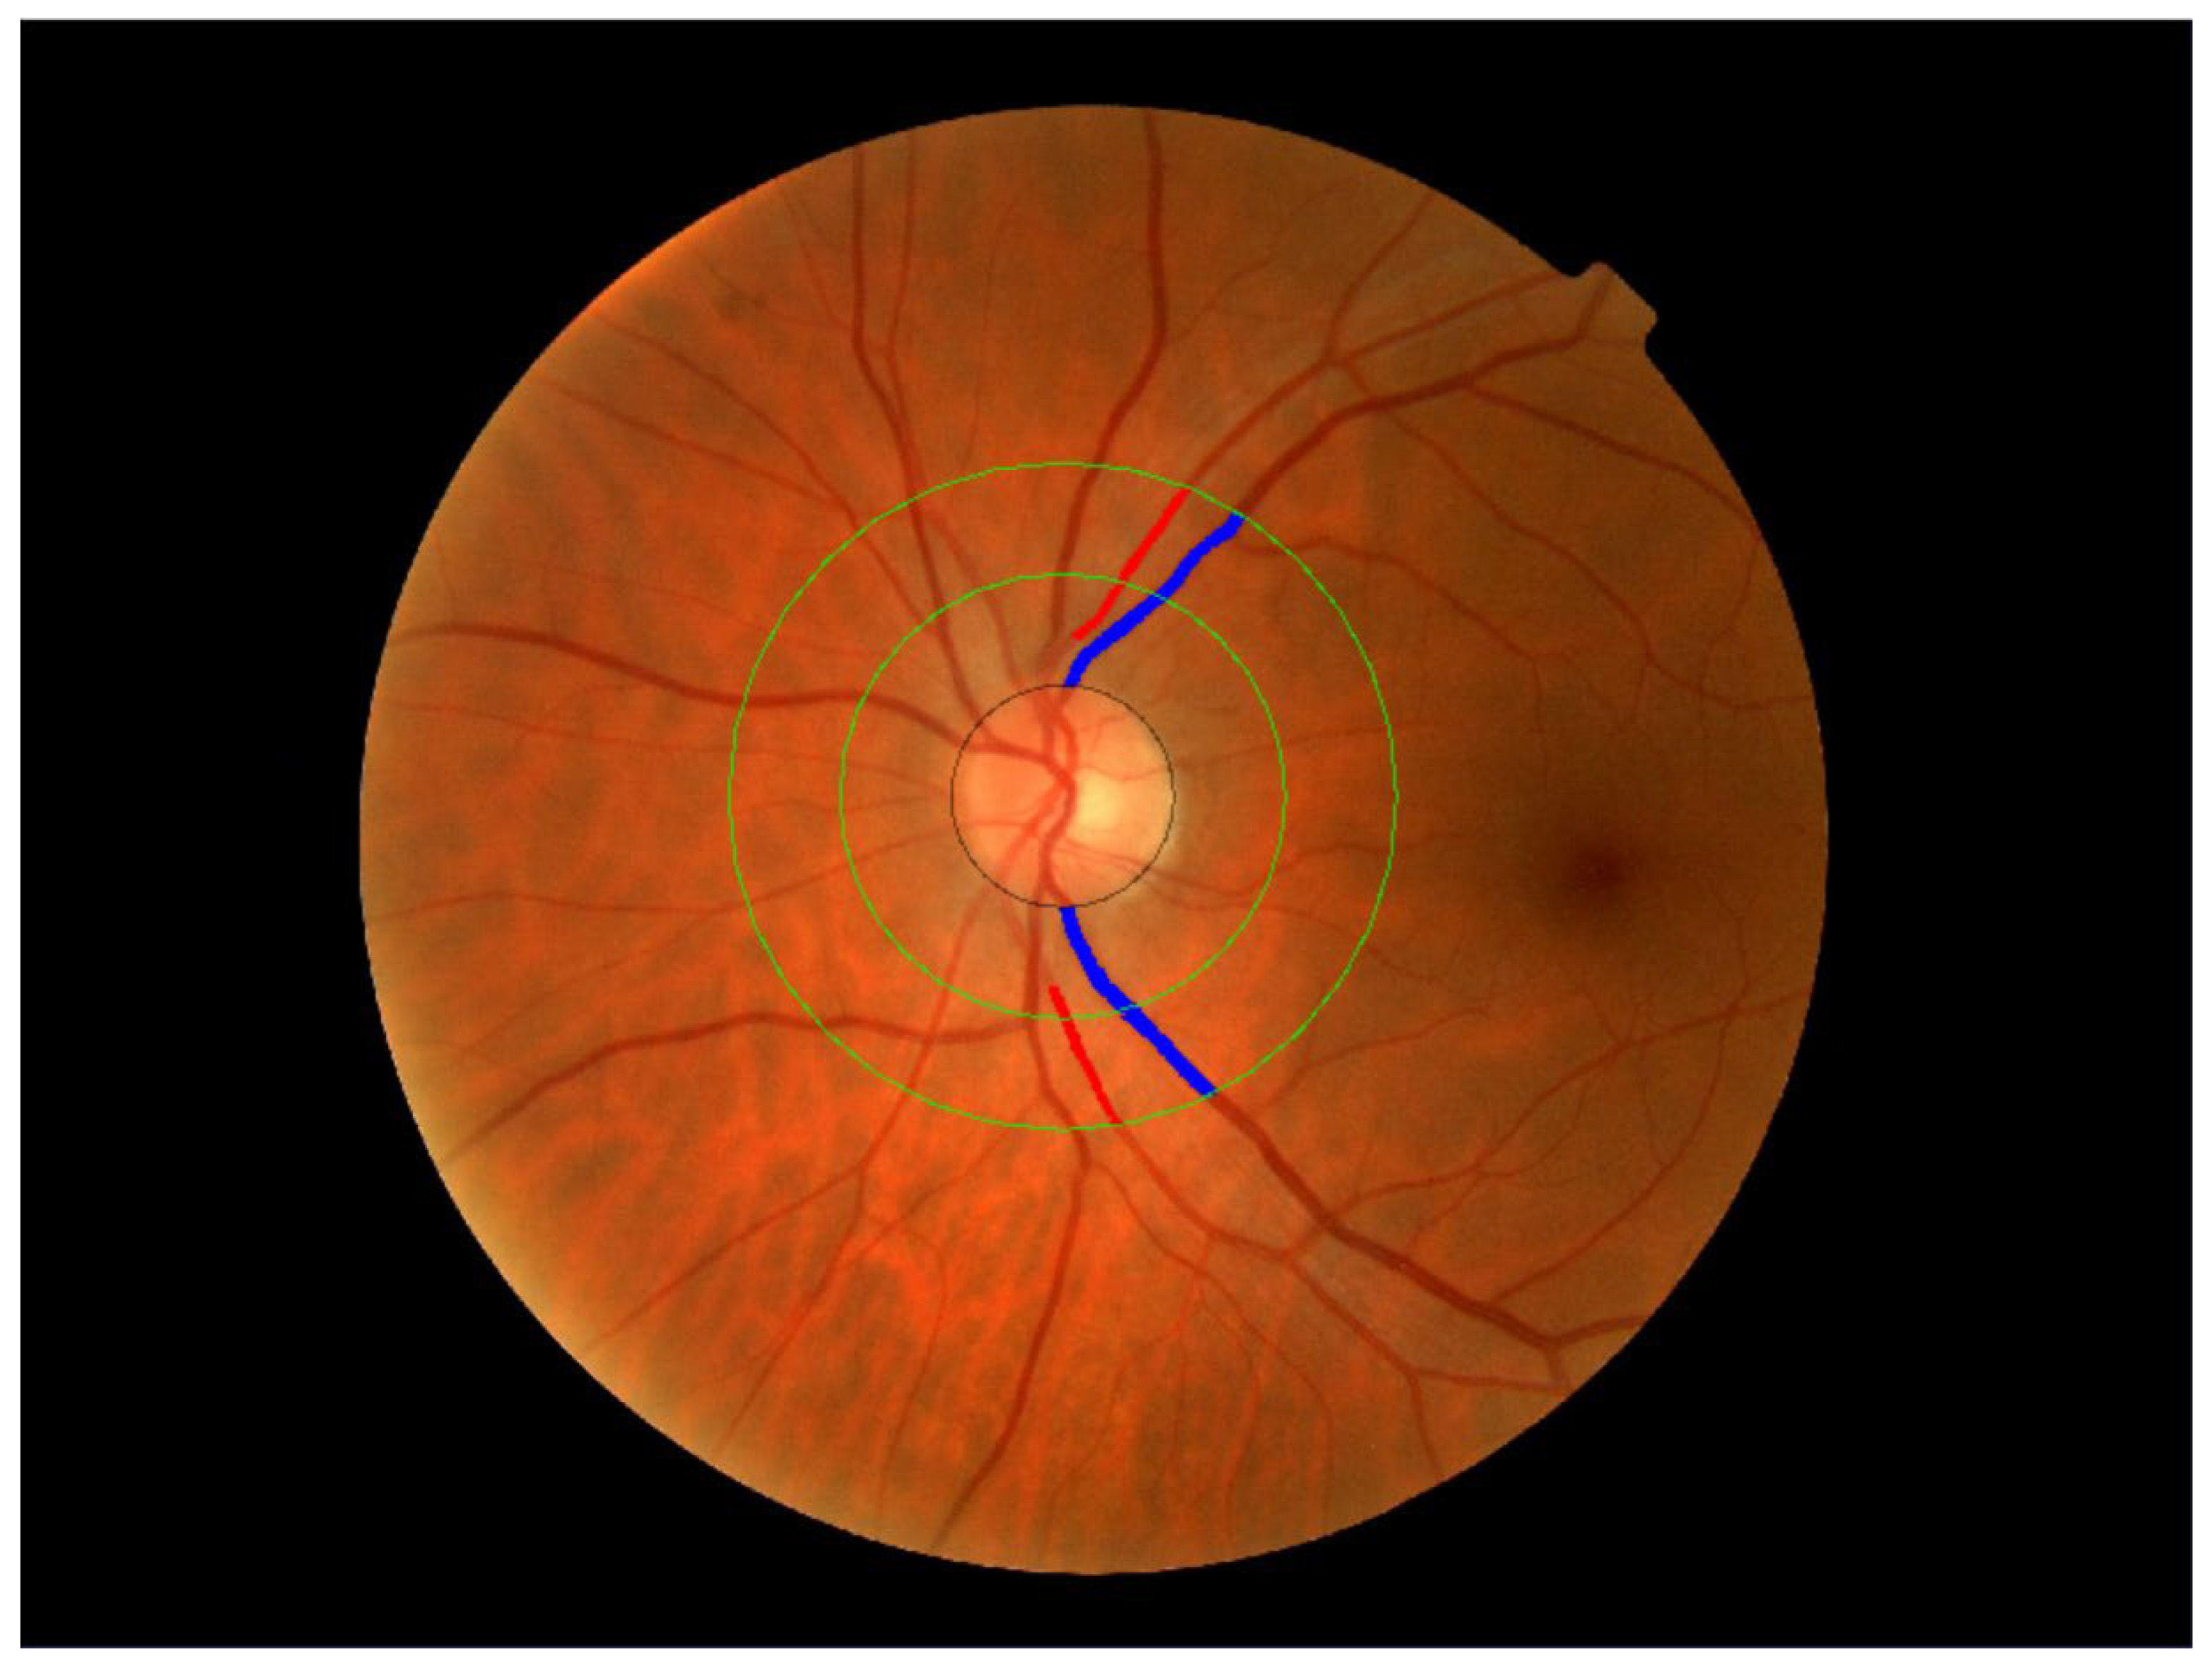

2.3.6. Retinal Vessel Assessment

- García-Ortiz, L.; Recio-Rodríguez, J.I.; Parra-Sanchez, J.; Elena, L.J.G.; Patino-Alonso, M.C.; Agudo-Conde, C.; Rodríguez-Sánchez, E.; Gómez-Marcos, M.A. A New Tool to Assess Retinal Vessel Caliber. Reliability and Validity of Measures and Their Relationship with Cardiovascular Risk. J. Hypertens. 2012, 30, 770–777. [Google Scholar] [CrossRef]